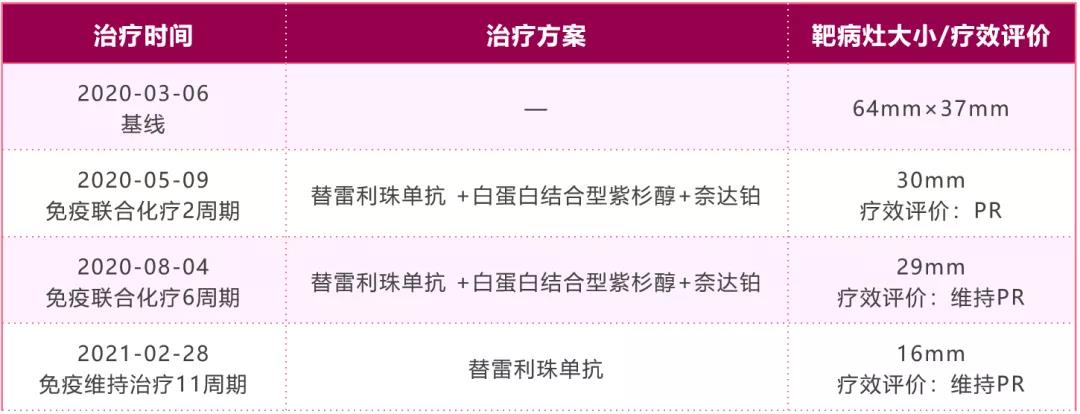

第一阶段:免疫联合化疗

治疗方案:经患者充分知情同意并签署知情同意书后,予“替雷利珠单抗+白蛋白结合型紫杉醇+奈达铂,q3w”治疗共6周期,其中第1周期方案为替雷利珠单抗200mg+白蛋白结合型紫杉醇100mg/m2 d1/8/15+奈达铂80mg/m2 d1,因出现Ⅲ度骨髓抑制,第2周期开始剂量调整为“替雷利珠单抗200mg+紫杉醇(白蛋白结合型)125mg/m2 d1/8+奈达铂80mg/m2 d1”。

影像学及疗效评价:联合治疗2周期后(2020年5月9日)胸部CT复查如图2-2所示,右肺上叶靶病灶最大径为30mm(治疗前靶病灶最大径为68mm),非靶病灶(纵隔淋巴结、胸膜、骨转移灶)仍可见,其中纵隔淋巴结病灶较前有所缩小。总体疗效评价PR。

联合治疗6周期后(2020年8月4日)胸部CT复查见右肺上叶靶病灶最大径为29mm,非靶病灶(纵隔淋巴结、胸膜、骨转移灶)仍可见,纵隔淋巴结病灶较前有所缓解。总体疗效评价维持PR。

治疗方案:患者经6个周期免疫联合化疗治疗,疗效维持在PR,予“替雷利珠单抗200mg,q3w”维持治疗,至今已维持用药11周期(共17周期)。

影像学及疗效评价:单药维持治疗11周期后(2021年2月28日)胸部CT复查如图2-3所示,右肺上叶靶病灶最大径为16mm,非靶病灶(纵隔淋巴结、胸膜、骨转移灶)仍可见。总体疗效评价维持PR。

本例患者以“右侧胸痛1月余,确诊右肺癌12天”来诊,诊断右肺肉瘤样癌Ⅳa期(cT3N2M1b)伴纵隔淋巴结、胸膜、骨转移,驱动基因阴性,PD-L1阳性,ECOG PS评分0分。经患者充分知情同意后,一线予患者替雷利珠单抗联合化疗后序贯为免疫单药维持治疗。患者经替雷利珠单抗联合治疗2个周期后,右肺靶病灶最大直径从68mm减少至30mm,瘤体缩小50%以上;纵隔淋巴结病灶较前有所缓解,总体疗效评价达到PR。联合治疗6个周期后,患者总体病情平稳,疗效维持在PR,治疗过程中曾出现过骨髓抑制,考虑化疗引起,予对症处理后可缓解。患者第二阶段予替雷利珠单抗单药维持治疗,用药至今已11周期(共17周期),右肺靶病灶较前进一步缓解,纵隔淋巴结病灶及骨转移病灶平稳,胸水明显减少,总体疗效持续稳定在PR,获得了较为持久的免疫应答,且单药维持期间未出现严重不良反应。截止发稿时,患者无进展生存期已达到1年余。

图2-4:病例二治疗方案及疗效评价